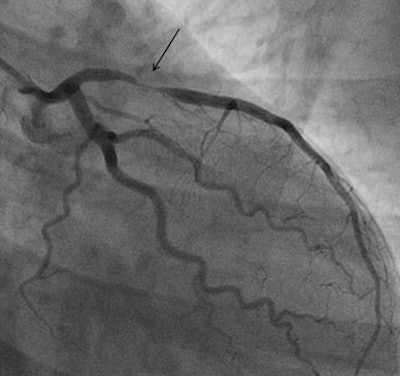

Invasive coronary angiography of the same patient. The black arrow shows a very tight narrowing in the proximal left anterior descending artery.They used the Bruce treadmill exercise protocol for the exercise stress echo, aiming to reach the maximum predicted heart rate. Standard images were acquired at rest and immediately after peak exercise. For the dobutamine stress echo, they used the standard 3 min stages protocol with incremental dobutamine doses of 5, 10, 20, 30 and 40 µg/kg/min. Ultrasound contrast was administered if at least two myocardial segments weren't seen on baseline echo images.